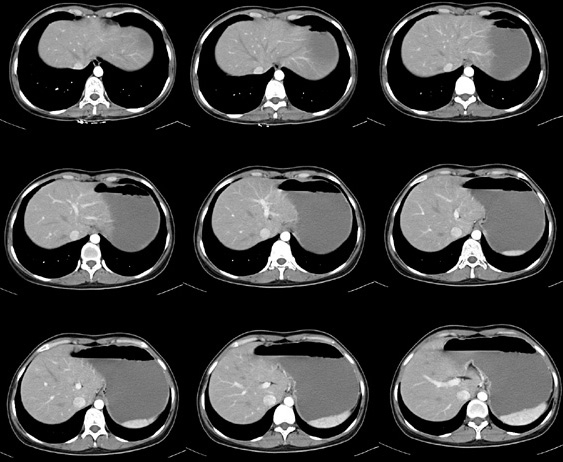

女性,28岁,停经3月,腹部膨隆1月,产前检查发现腹部占位

{肿块中心ct值27hu,增强后,动脉期、门脉期均无明显强化)

患者手术病理:腹腔囊性淋巴管瘤,象这样充满整个腹腔的的确很少见